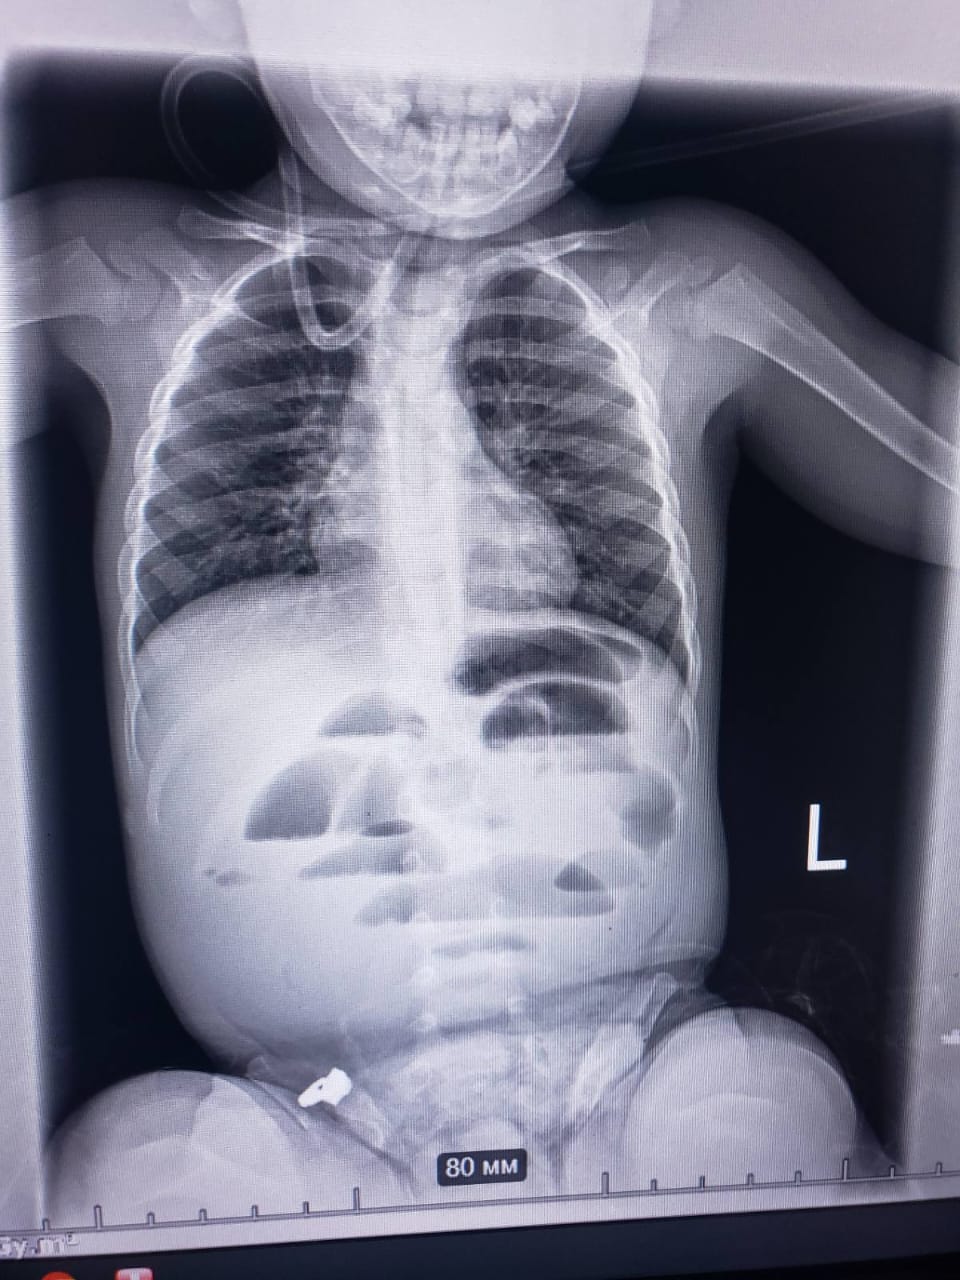

В Региональный медицинский центр семейного здоровья доставили ребенка возрастом 1 год 8 месяцев с подозрением на кишечную непроходимость. На рентгенограмме органов брюшной полости признаки непроходимости подтвердились.

Было принято решение провести срочную операцию. Во время нее выявили постороннее тело, полностью перекрывавшее просвет кишечника, – гидрогелевый шарик до 3 сантиметров в диаметре. После удаления инородного тела и наложения узловых швов ребенка перевели в отделение интенсивной терапии.